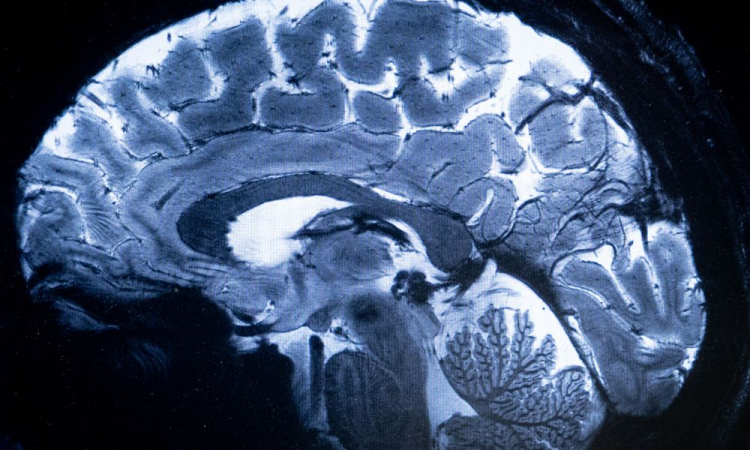

O scanner de ressonância magnética (IRM) mais potente do mundo conseguiu escanear o cérebro com um nível de precisão jamais visto, uma proeza que pode ser decisiva para detectar doenças. “Vimos um nível de precisão nunca antes alcançado no CEA”, disse Alexandre Vignaud, um físico que trabalha no projeto. Pesquisadores da Comissão de Energia Atômica (CEA) francesa utilizaram pela primeira vez a máquina para escanear uma abóbora em 2021. Recentemente, as autoridades sanitárias deram sinal verde para escanear humanos, e cerca de 20 voluntários saudáveis se ofereceram para que seus cérebros fossem escaneados em Saclay, subúrbio ao sul de Paris.

O campo magnético criado pelo scanner é de 11,7 teslas, uma unidade de medida nomeada em homenagem ao inventor Nikola Tesla. Essa potência permite que a máquina escaneie imagens 10 vezes mais precisas que os IRM normalmente utilizados em hospitais, cuja potência geralmente não supera os três teslas. “Com essa máquina podemos ver os pequenos vasos que alimentam o córtex cerebral, ou detalhes do cérebro que eram quase invisíveis até agora”, disse.